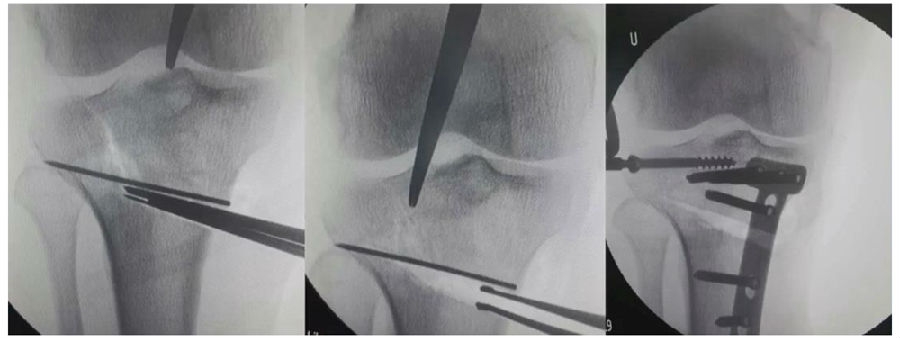

(3)拉力钉技术

第3个原因和拉力钉使用技术有关。拉力螺钉的使用是希望在合页端产生一个加压的效果,如果拉力螺钉使用过度,会出现合页端拉断的情况,导致Ⅱ型骨折。所以要求拉力螺钉在使用时加压不要过度,通常当钢板有轻微的变形即可,不要过度加压。

因为外侧合页周围有软组织,即使是说骨性合页断了,但是由于软组织合页还在,所以只要用拉力螺钉复位固定,维持好力线即可。术后患者正常康复,预后较好。

(2)Ⅱ型骨折

当出现Ⅱ型骨折时要特别注意,因为此时截骨的远端就是骨折的远端,近端只有上胫腓周围骨筋膜存在,所以相对来说Ⅱ型骨折并不稳定。

首先用拉力螺钉复位,调整好力线。然后做结构性植骨,延迟负重,所谓延迟负重就是延迟到外侧合页和上行截骨线处达到初始愈合,然后再让患者进行负重。如果不做结构植骨加延迟负重,就会出现一些非常严重的现象,如不愈合。

拉力钉复位,结构性植骨

左侧患者未植骨正常负重,术后4个月不愈合;右侧患者非结构性植骨过早负重,术后1年未愈合